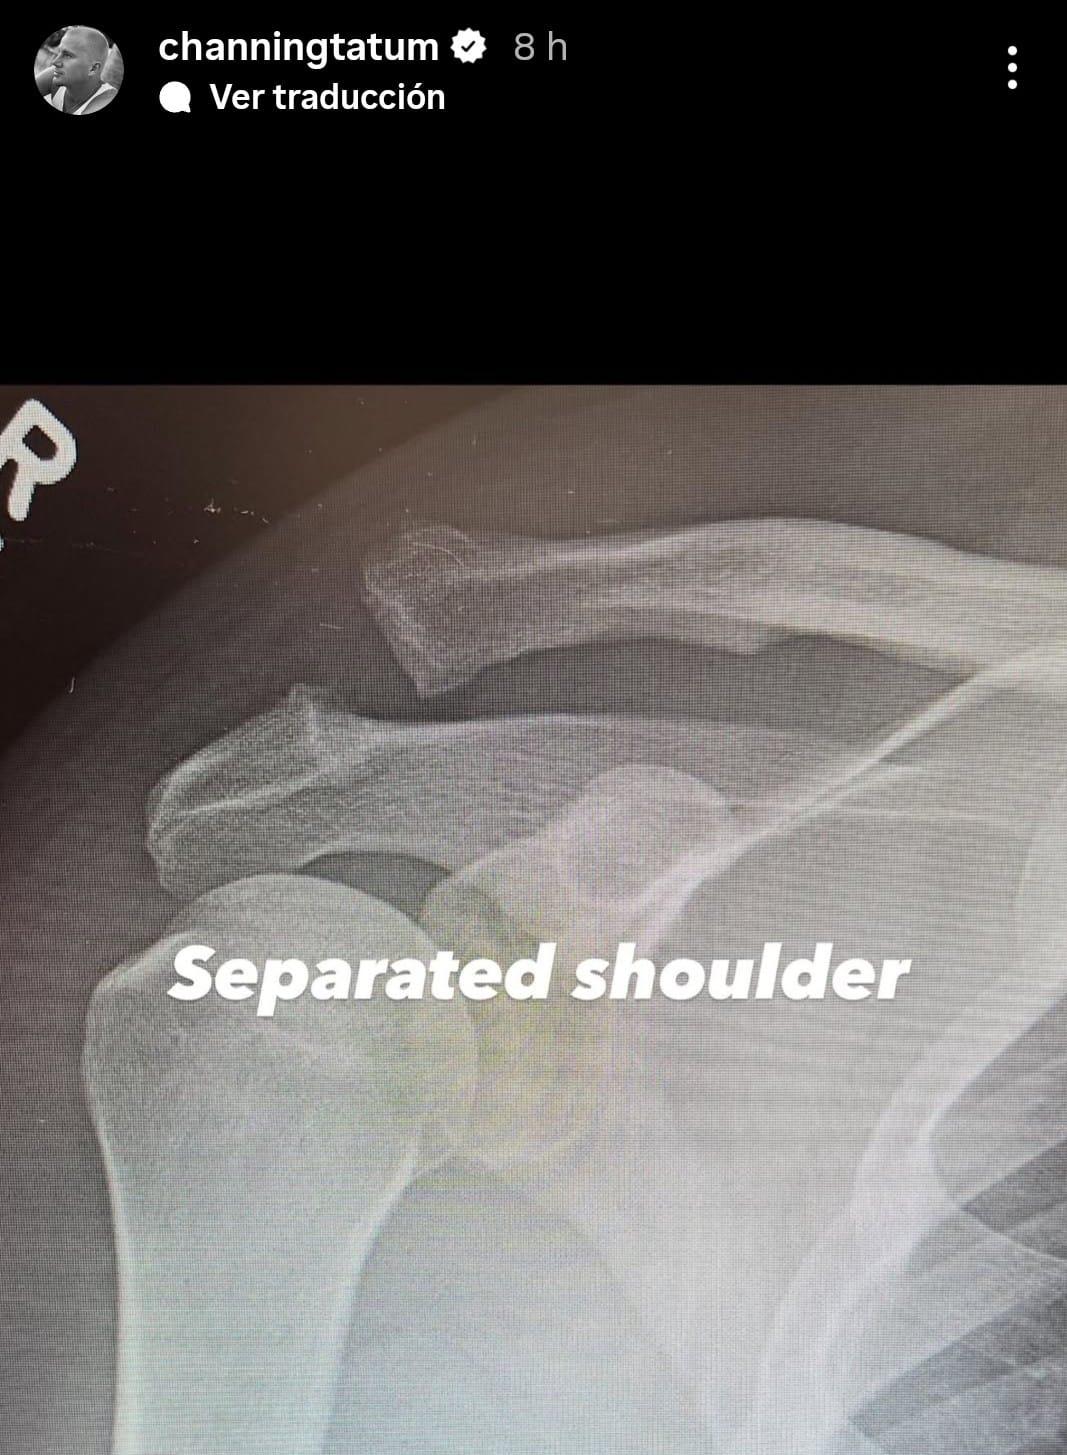

Posteriormente, el actor explicó con más detalle el motivo de su hospitalización a través de sus Historias de Instagram. En una primera publicación, compartió una radiografía de la parte superior de su brazo y del hombro, donde se podían apreciar dos huesos rotos. “Hombro separado”, escribió junto a la imagen.

Radiografía del hombro de Channing Tatum antes de ser operado.